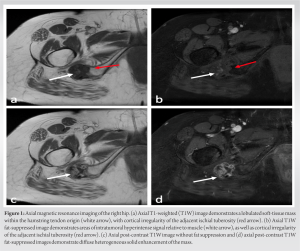

X-rays taken at an external medical institution displayed soft-tissue calcification in the region of the ischial tuberosity, extending just distally into the right ischial tuberosity. This prompted further investigation through MRI. A review of the axial MRI findings (Fig. 1) revealed a well-defined, lobulated heterogeneous soft-tissue mass measuring 6.9 × 3.1 × 2.7 cm within the origin of the right hamstring tendon. The mass exhibited intermediate signal intensity on T1-weighted (T1W) sequences, resembling the signal intensity of skeletal muscle, with some areas of decreased signal intensity. Post-contrast T1W fat-saturated sequences showed intermediate signal intensity with no surrounding edema (Fig. 1d). The lesion extended toward and caused cortical irregularity of the adjacent right ischial tuberosity, which was evident on coronal MRI (Fig. 2). Post-contrast imaging demonstrated solid heterogenous enhancement of the soft-tissue mass, along with scattered areas of low signal intensity on T1W sequences, due to intralesional calcifications (Figs. 1 and 2). To further investigate the mass, a CT-guided biopsy was performed, and the scout view (Fig. 3) showed lobulated calcified mass near the right ischial tuberosity.

In our case, the imaging findings of the CCMN revealed an amorphous calcified mass projecting inferiorly to the right ischial tuberosity on radiographs. MRI showed cortical irregularity of the ischial tuberosity and demonstrated a calcified low to intermediate T1W signal intensity intratendinous soft-tissue mass within the hamstring tendon origin. The mildly increased T1W signal within the tumor may be attributed to a combination of intratumoral protein content and T1 shortening due to surface interactions between microcalcifications and protons [7,8]. In addition, intralesional foci of high signal intensity were observed on proton density images, which likely corresponded to the chondroid/cartilaginous matrix of the neoplasm. Notably, there was minimal perilesional edema on fluid-sensitive sequences, which serves as a distinguishing feature from acute calcific tendinitis. Post-contrast imaging revealed a heterogeneously enhancing solid soft-tissue mass. The scattered internal foci with low signal intensity on both T1 and PD sequences were suggestive of internal mineralization within the mass. CT images (Figs. 3 and 4) further revealed mass-like amorphous calcifications within the right hamstring tendon origin, causing cortical irregularity in the adjacent ischial tuberosity.